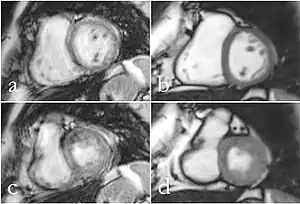

Although applications of real-time MRI cover a broad spectrum ranging from non-medical studies of turbulent flow[27] to the noninvasive monitoring of interventional (surgical) procedures, the most important application making use of the new capabilities is cardiovascular imaging.[1] Previous cardiac MR (CMR) used cine techniques to capture the periodic motion of the heart. However, this is not feasible for patients with arrhythmia, where the cardiac cycle is unpredictable.[28] With the new method it is possible to obtain movies of the beating heart in real time with up to 50 frames per second during free breathing and without the need for a synchronization to the electrocardiogram.[29] A study performed by Laubrock et al.[28] demonstrated that RT-MRI produced higher quality images with a higher SNR than cine CMR with a bSSFP sequence and radial k-space sampling. RT-MRI also removes the need for breath-holding while imaging, leading to a more comfortable experience for the patient as well.[28]